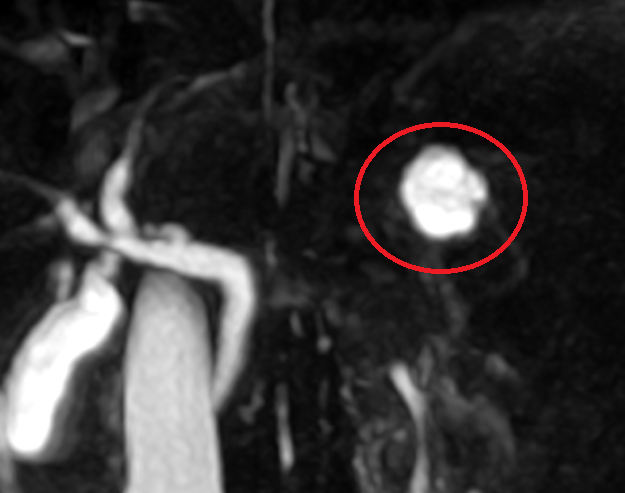

진료 후 췌장 MRI를 진행하였습니다. MRI상 췌장 꼬리쪽으로 고신호를 가진 2cm크기의 물혹이 관찰됩니다. 이 물혹은 췌관과의 연결성도 보이고 있어, 전암성병변으로 확인되는 췌관내유두점액종양으로 판단이 되며, 이에 대해서는 추가적인 치료를 위해 상급병원으로 전원하였습니다.

한마디: 췌장낭종에서 점액성 낭종과 췌관내 유두 점액성 종양은 암으로 발전이 가능한 전암성 병변입니다. 크기가 2cm으로 추가 치료가 필요한 상태입니다.

• 췌장MRI: 췌관 연결성 확인 췌장MRI: 췌관 연결성 확인